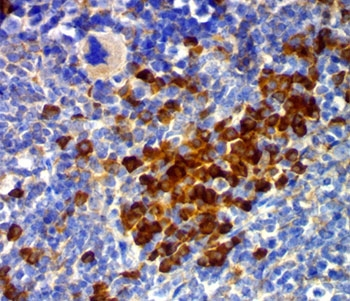

CD63 Antibody / LAMP-3 [orb2637613]

FACS, IF, IHC-P, WB

Human, Mouse

Mouse

Monoclonal

Unconjugated

100 μg